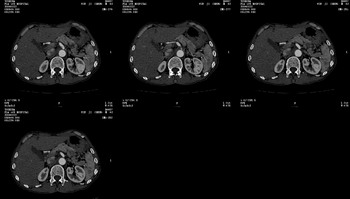

男 62 夜间突然腹痛并向背部放射 ,急诊疑胰腺炎 ,胰淀粉酶正常 ,ct示胰腺未见明显异常,发现降主动脉密度欠均,做主动脉造影示胸腹主动脉半月形低密度充盈缺损,内膜钙化并内移,累及腹腔干致根部明显狭窄,未见明显破裂口。 本人为是不典型夹层,其他人有说是动脉硬化或动脉炎的。请大家发表一下看法。

可惜图像太小,但结合病人年龄、病史及降主动脉壁增厚及模糊表现应该考虑,在我看到的急性主动脉夹层别人中血管壁都有这样改变。

我觉得这个不像主动脉夹层,应该是血栓多点,如果可以重建个mpr也许对诊断更有帮助。